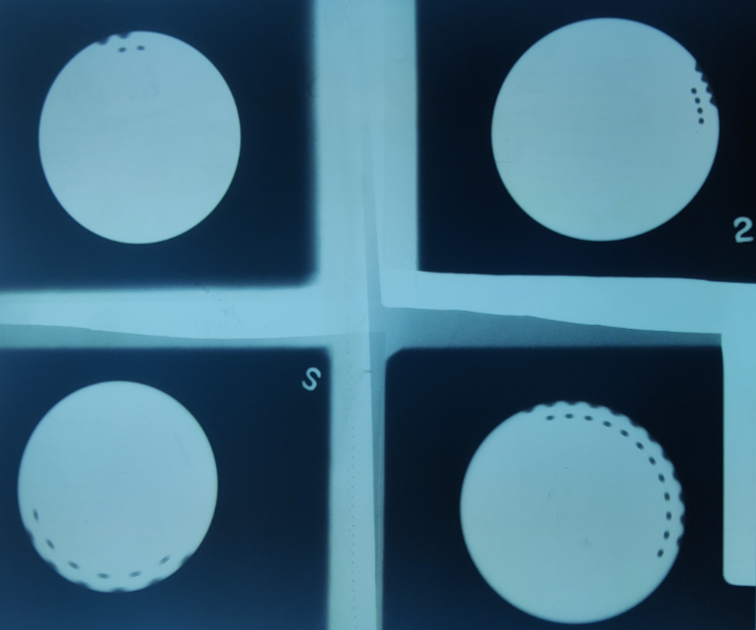

What is this test?

Images from a manual spinning top (single-phase) timer test. Used to test the time of exposure

Q

Images from a synchronous/electronic timer (3-phase/HF) test. Used to test the time of exposure